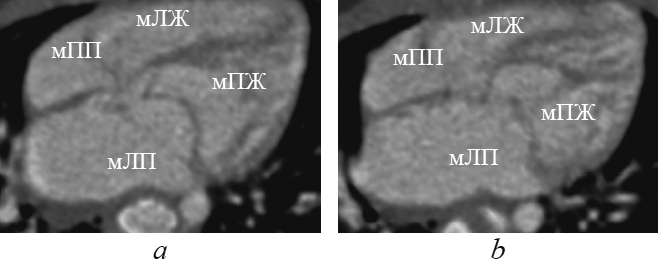

В данной статье приведены результаты анализа данных рентгеновской компьютерной томографии с внутривенным болюсным введением контрастного вещества детей с транспозицией и корригированной транспозицией магистральных артерий путем последовательного построения многоплоскостных реформаций, ориентированных на оси сердца. Из 148 детей со сложными врожденными пороками сердца и магистральных артерий транспозиция магистральных сосудов встречалась у 13 пациентов (в возрасте от 1 до 144 дней жизни; 9 — мужского пола, 4 — женского пола), корригированная транспозиция магистральных сосудов — у 4 пациентов (в возрасте от 6 мес. до 15 лет 6 мес.; 2 — мужского пола, 2 — женского пола). В статье подробно описаны анатомические характеристики, на основе которых определяется морфология каждой камеры сердца, и реформации, в которых они оцениваются. В статье приводится сравнительная характеристика структур сердца и магистральных артерий при транспозиции и корригированной транспозиции магистральных артерий в каждой отдельно взятой реформации, ориентированной на оси сердца. По результатам анализа последовательно построенных реформаций, ориентированных на оси сердца, указаны и проиллюстрированы характерные анатомические признаки транспозиции и корригированной транспозиции магистральных сосудов. Установлено, что из перечня предлагаемых реформаций, ориентированных на оси сердца, характерные анатомические признаки транспозиций достоверно определяются в следующих реформациях: по длинной оси приносящего тракта правого желудочка; левых камер сердца; приточных отделов желудочков; по короткой оси на уровне магистральных сосудов. Многоплоскостные реформации, ориентированные на оси сердца, на основе данных КТ-ангиокардиографии позволяют дать полную и точную анатомическую оценку сердца и магистральных сосудов, что важно при планировании оперативного вмешательства при врожденных пороках сердца.